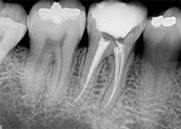

antes depois